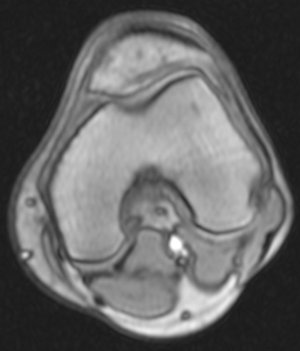

Недавно,5 сентября получил травму на работе. Выходя из транспорта почувствовал резкую боль с внутренней стороны колена (как бы ножом режет). Весь день не мог нормально поднять ногу. Особенно боль проявлялась при спуске по ступенькам. Через 3 часа после травмы обратился в травмпункт. Там сделали рентгенный снимок и сказали, что все впорядке. На следующий день весь коленный сустав с внешней стороны стал как бы после заморозки (холодить изнутри). Через дней 5-6 боль притупилась, а еще через несколько дней прошла. Но сустав все еще морозит изнутри. При резких движениях ощущения что кости сустава выходят и входят обратно на свое место. И сустав как будто чугунный. 8 октября сделал МРТ (так как большие очереди пришлось месяц прождать). Врач делавший МРТ сказал что дислокация коленной чашечки. К травмотологу только через неделю записан. Может подскажите что это? И последнее, сегодня начал морозить изнутри и сустав другой ноги. И холодок теперь идет от колена и вниз аж до пальцев на обеих ногах. Как бы онимения. Теперь не могу пробежать и нескольких метров такое ощущения что ниже колена мышцы как деревянные. Вот некоторые снимки МРТ. Рентген будет завтра на руках, если понадобится. Есть ли на самом деле смещение коленной чашечки?